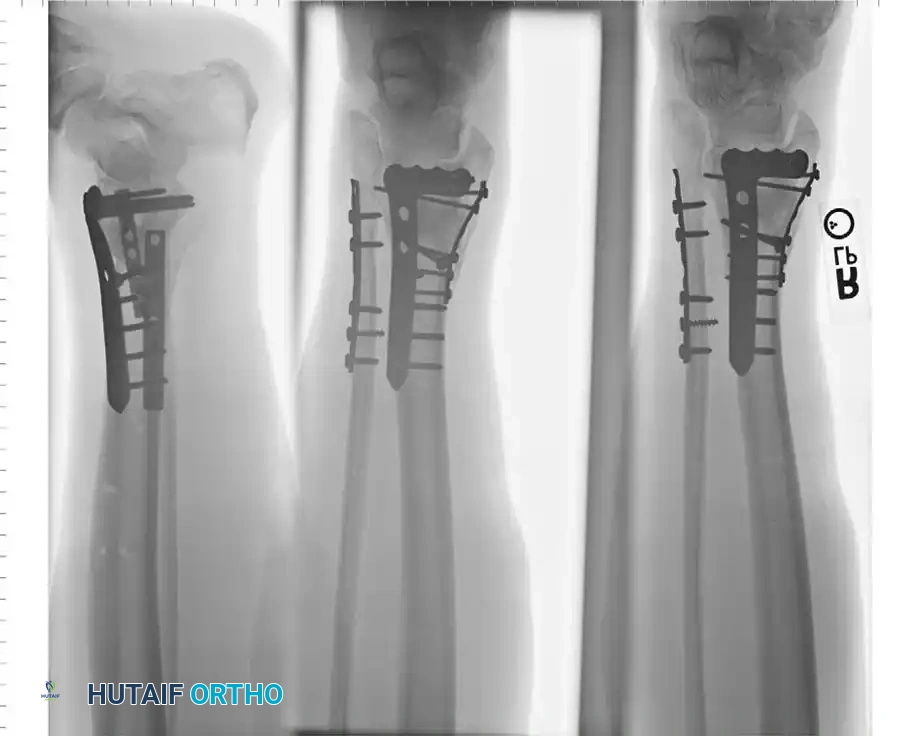

Surgical Sequence for Bimalleolar Fixation

- Lateral Side First: The fibula is typically addressed first to restore the length and rotation of the lateral column. This often indirectly reduces the talus and simplifies the medial reduction.

- Medial Side Second: Once the lateral mortise is established, the medial malleolus is directly reduced and fixed.

- Syndesmotic Evaluation: After bimalleolar fixation, the syndesmosis must be tested using the "Cotton test" (lateral traction on the fibula using a bone hook). If widening occurs, syndesmotic screws or flexible suture-button constructs are required.